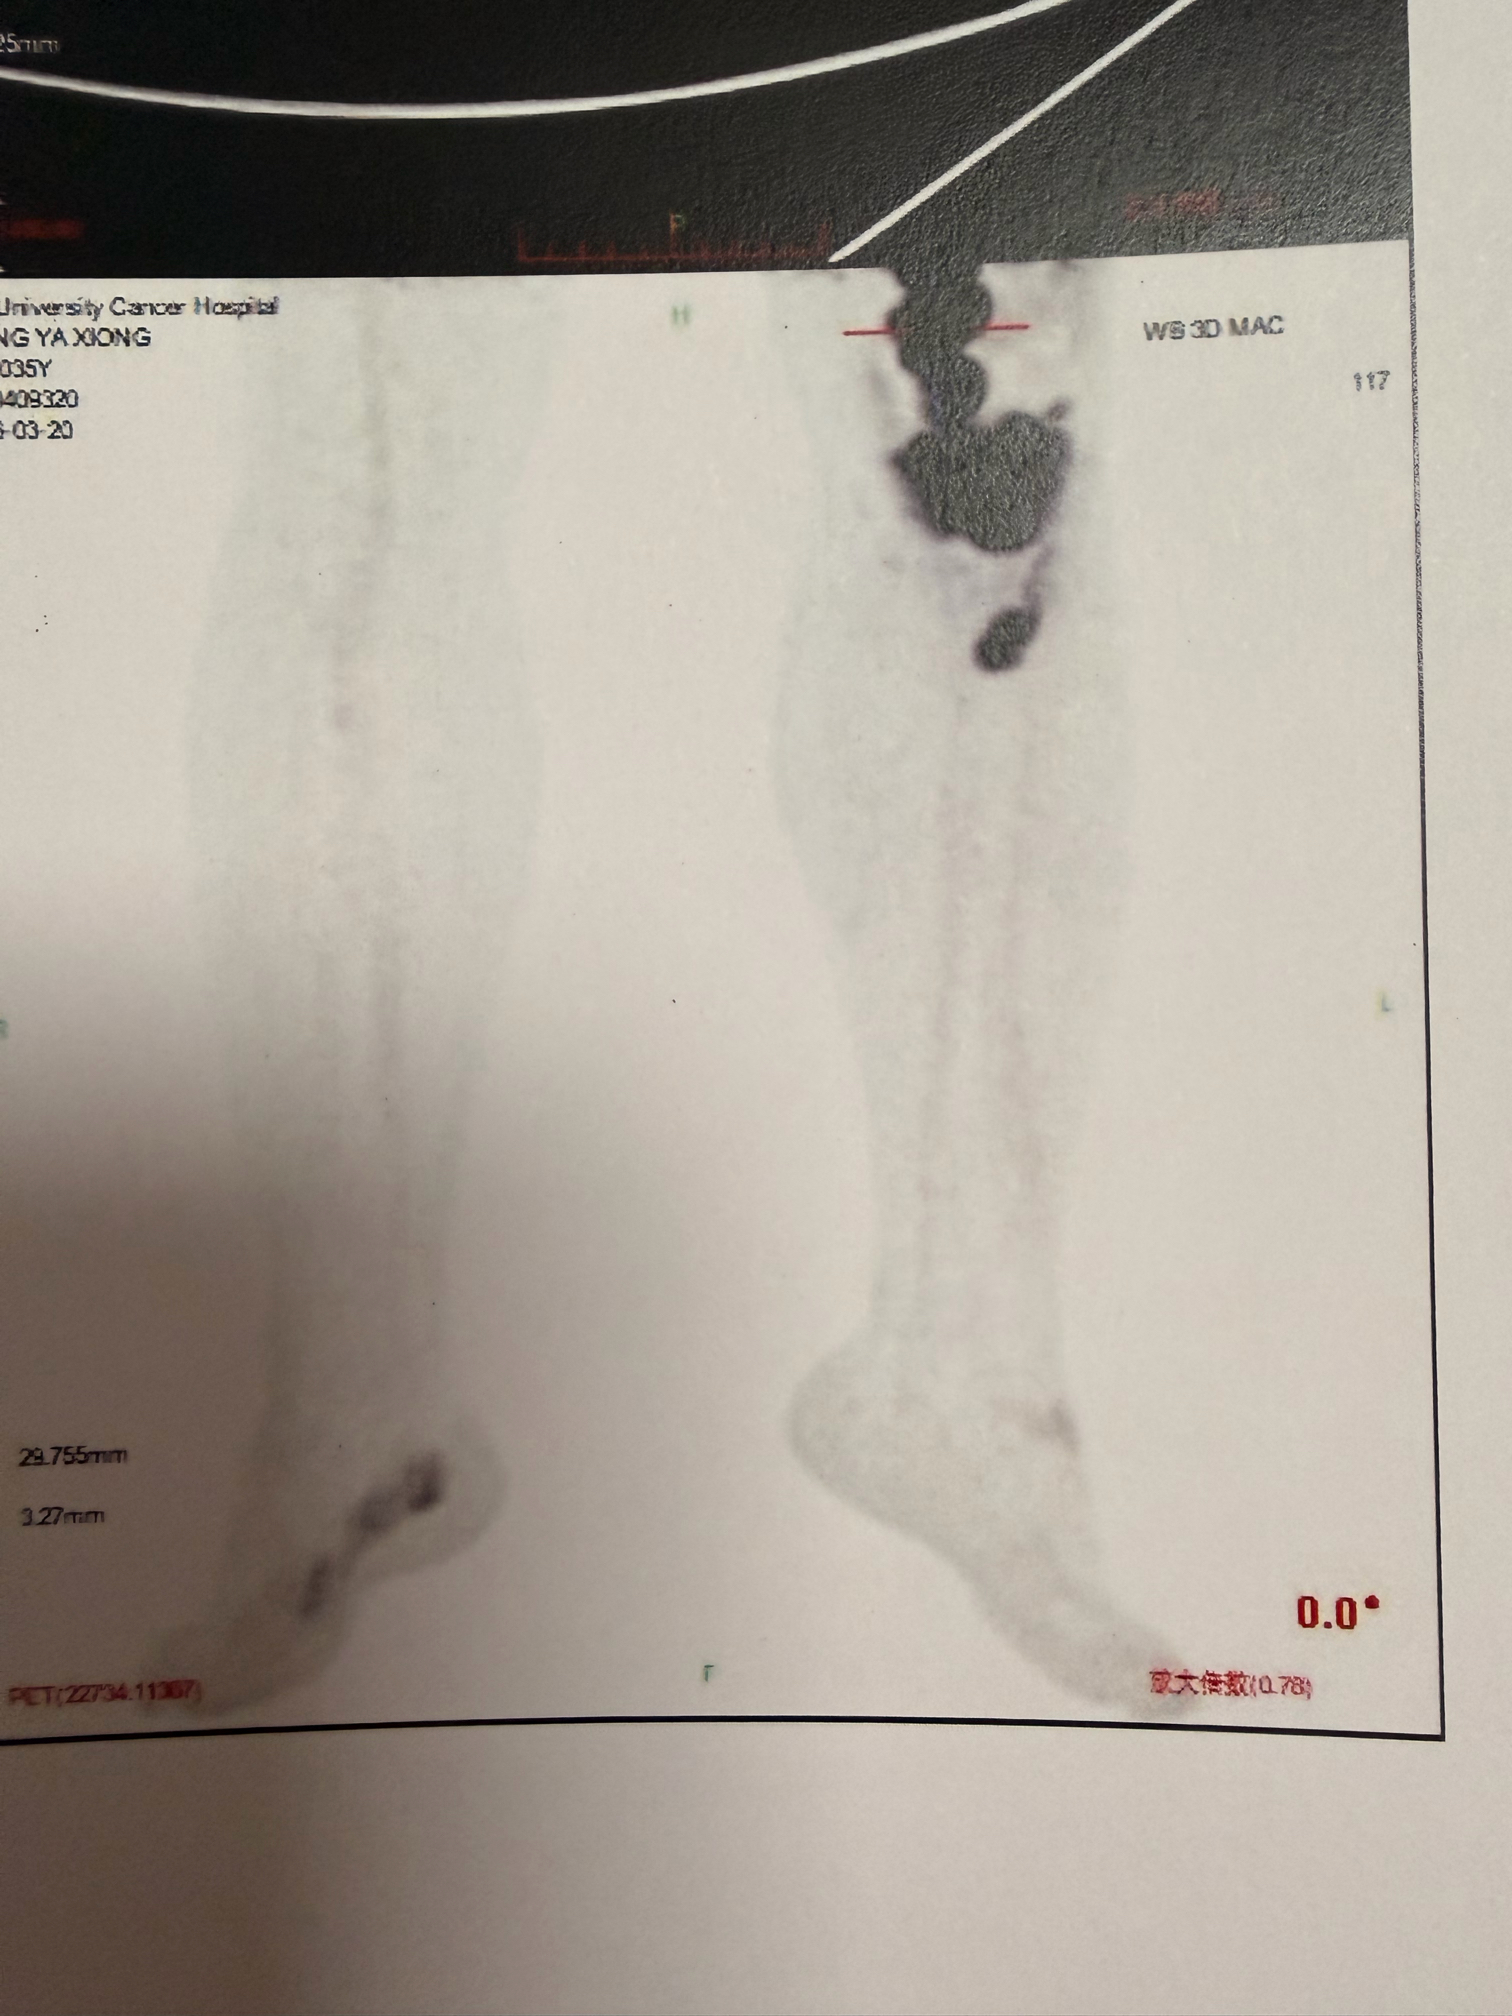

弥漫大B,IV期,骨髓侵犯,GCB型,伴CD5+,myd88和CD79b变异

petCT显示很多地方都累及

骨穿报告显示累及骨髓